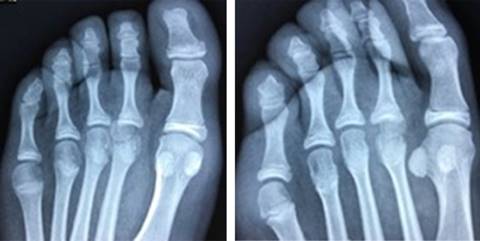

Se realizan radiografías anteroposterior (AP) y oblicua del pie (Figura 1). Se encuentra fractura epifisiaria desplazada de la cabeza del segundo metatarsiano.

Figura 1: Radiografías anteroposterior y oblicua del pie derecho, en la cual se encuentra fractura desplazada de la epífisis del segundo metatarsiano.